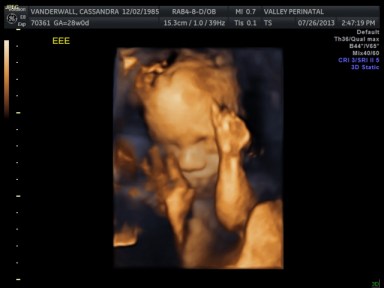

All of their organs (kidneys, bladders, hearts, brains, stomachs) look great and are also appropriate sizes. The blood flow to Elle has improved and has stabilized. All heart rates remain within normal limits, and are often on the higher side, which is probably because they just can’t sit still. We are truly excited to meet our little wiggle worms!